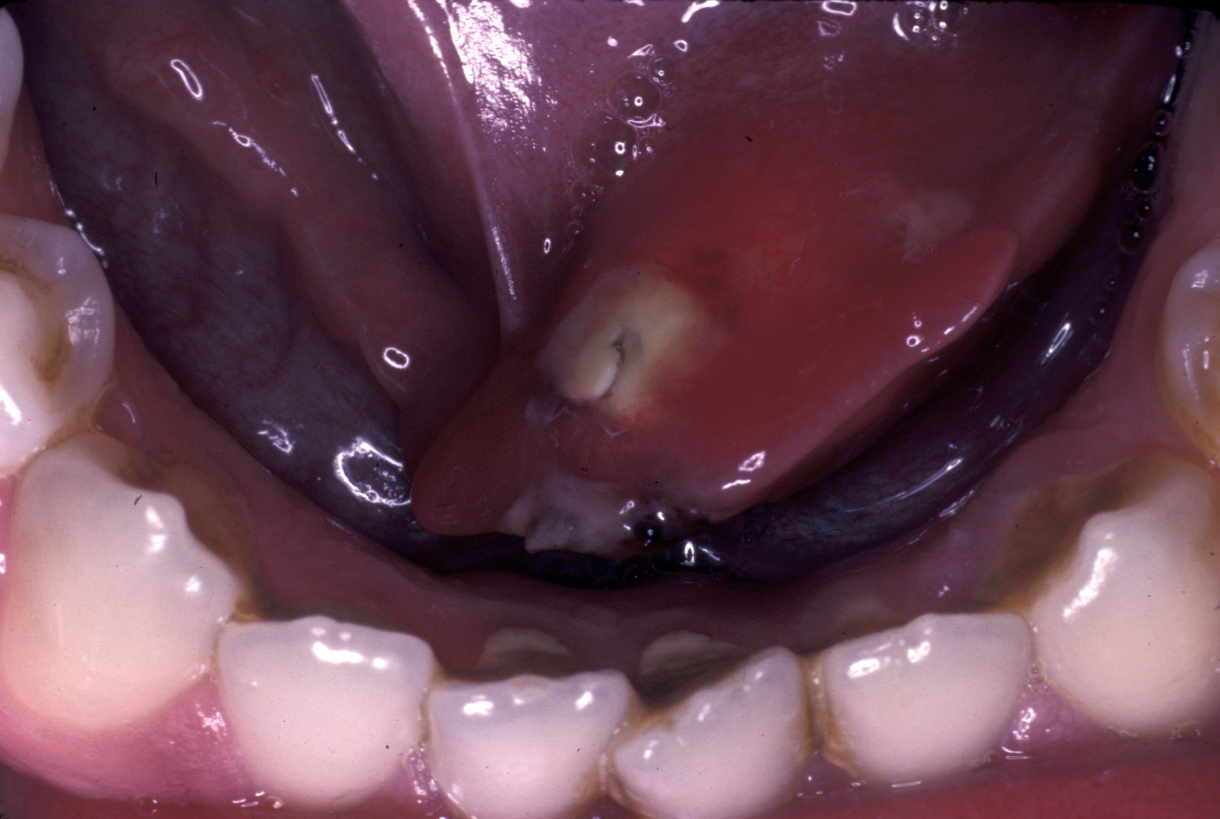

Pus may be discharging from the papilla (see Figure 5). If not, the gland should be milked to obtain pus for microbiology. Abscess formation may be a (rare) sequela (develop as a consequence of the initial condition).

Figure 5: Pus discharging at the parotid duct.